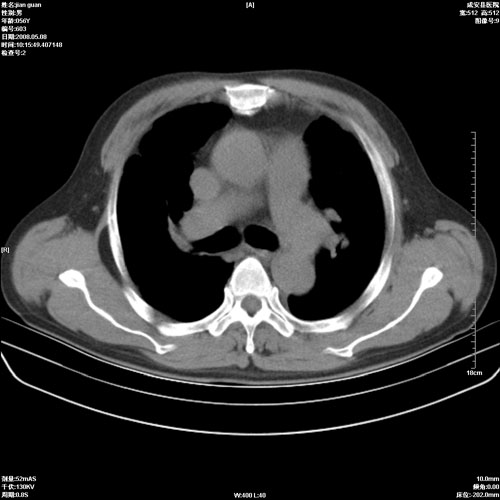

病人 男 60岁 主诉 胸闷 无明显发热 一般情况尚可。

考虑1心功不全,肺水肿

2右上肺结核纤维性病灶、肺气肿

1.右上肺陈旧性肺结核.

2.心脏增大(以左心室增大为著),请结合b超及听诊.

1.两上肺陈旧性结核;慢支肺气肿。

2.肺门血管扩张,心脏增大,为肺心病

考虑.两上肺陈旧性结核;慢支肺气肿。肺心病

1.陈旧肺结核;

2.慢支肺气肿;

3.肺心病.

陈旧性肺结核,左心房扩大,左心衰竭

2右上肺结核纤维性病灶、肺气肿 ,肺心病